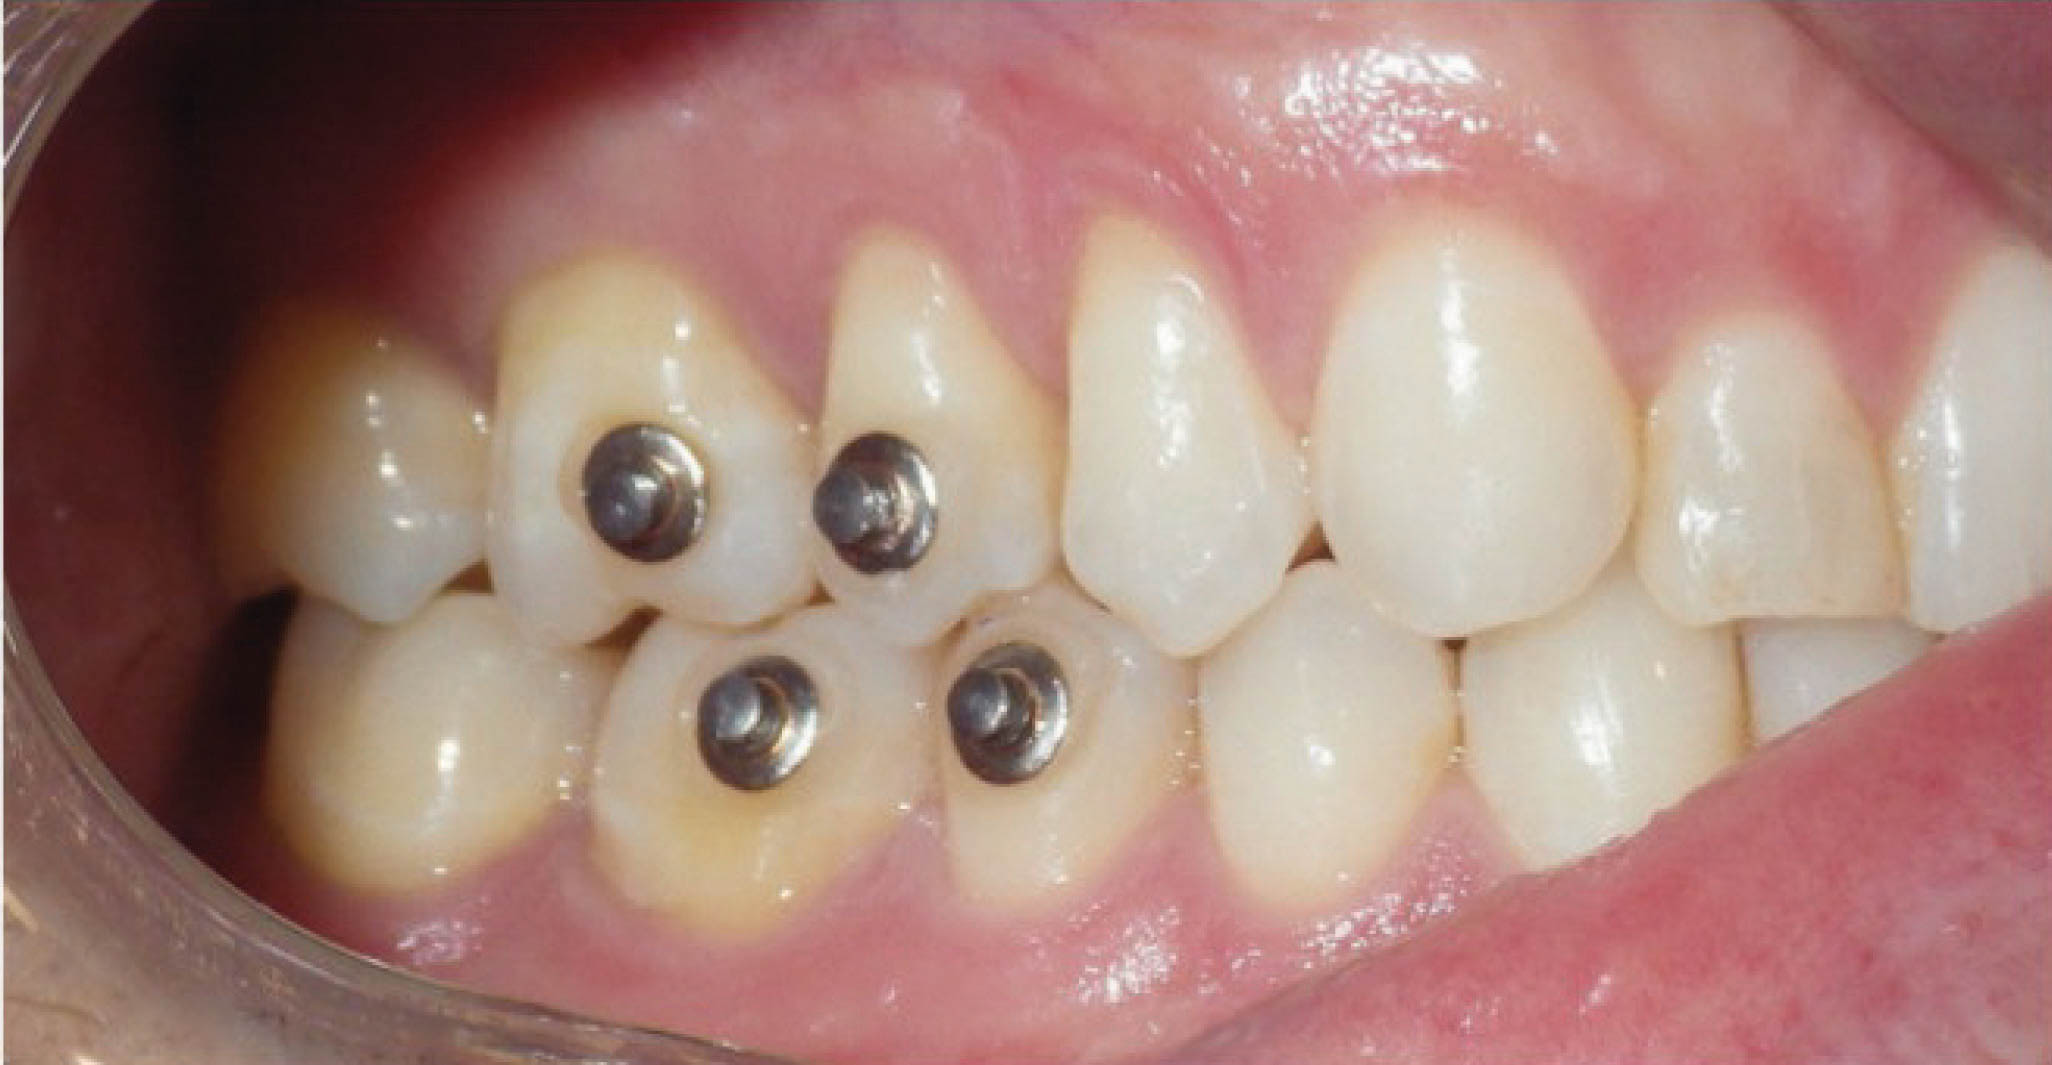

برای کانین چپ بالا درخواست ۳۰ درجه تیپ بیشتر میکنیم ولی انتظار رسیدن به چنین تیپی را نداریم. فقط میخواهیم که نیروی مناسبی روی کانین چپ بالا باشد تا حرکت ریشه هم داشته باشیم. شکل 165-6 یک سال بعد بیمار را نشان میدهد. همانطور که در عکس OPG میبینید حرکت بادیلی کانین چپ بالا رخ داده است. در واقع هنوز یک کمی ریشه مزیالی است که در قالبگیری جدید در خواست ۳۰ درجه زاویه بیشتر نمودیم. در ماه ۲۰ درمان فضا برای قرار دادن ایمپلنت آماده شده است (شکل 166-6).

شکل 164-6

شکل 166-6